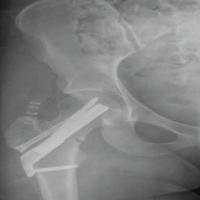

Vertical humeral traction was reduced in an arm sling; there is no need for any reduction manoeuvers [9]. The Watson rehabilitation protocol was followed. It advises retraining specific scapular motor control before any rotator cuff/deltoid strengthening [10,11]. At the end of a 10-week period, follow-up radiographs revealed that the humeral head had been repositioned into the glenoid (Fig. 3 and 4), and the active range of motion had significantly improved to 90° abduction with possible overhead abduction. External rotation had also improved to 80°.